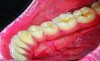

The MGJ was delineated by the visual method and the roll method following clinical examination in dental chairs appropriately equipped. Visual assessment relies on identifying the color difference between the gingiva and alveolar mucosa. The mucosa beyond the MGJ typically appears darker red compared to the AG, helping to demarcate the MGJ. The rolling probe method entails pushing the neighboring alveolar mucosa coronally with the blunt end of a probe. It is a functional assessment method that aids in determining the boundary between gingiva and movable mucosa.10 The probing sulcus depth was subtracted from the measured KG width at the mid-lingual aspect of each tooth to determine the width of AG, and all fractional measurements were rounded off to the nearest whole number of millimeters (Figure 1 through Figure 3).

Fig 3 = determining width of keratinized gingiva.

Figure 3

Fig 4 through Fig 6. Lingual attached gingiva in a male subject: Fig 4 = left side.

Figure 4